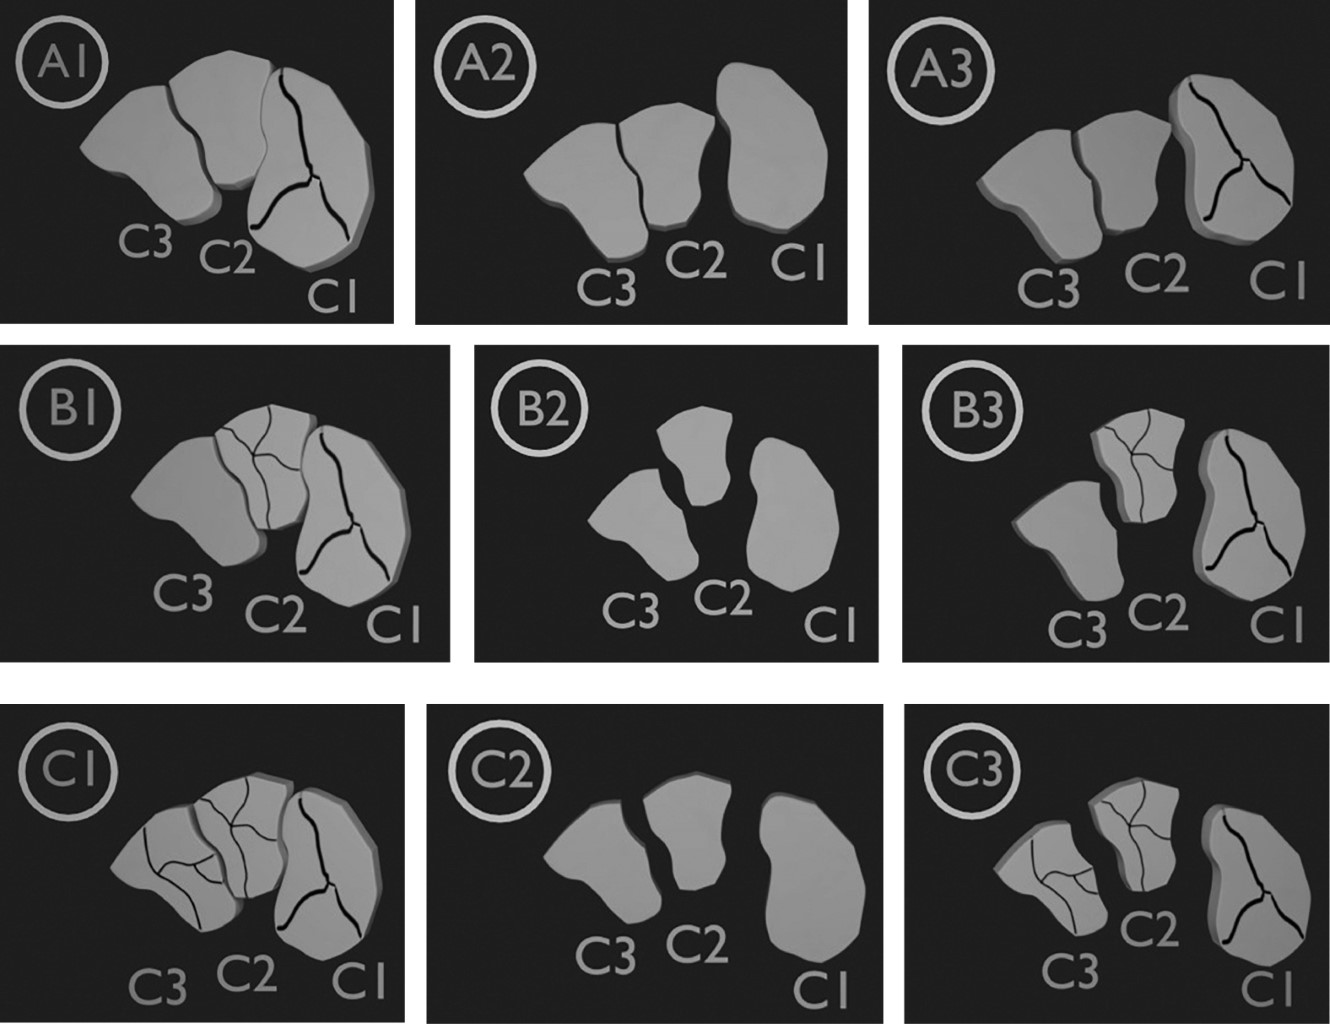

20. Mehlhorn AT, Schmal H, Legrand MA, Südkamp NP, Strohm PC. Classification and outcome of fracture-dislocation of the cuneiform bones. J Foot Ankle Surg. 2016; 55(6): 1249-55. doi: 10.1053/j.jfas.2016.01.019.